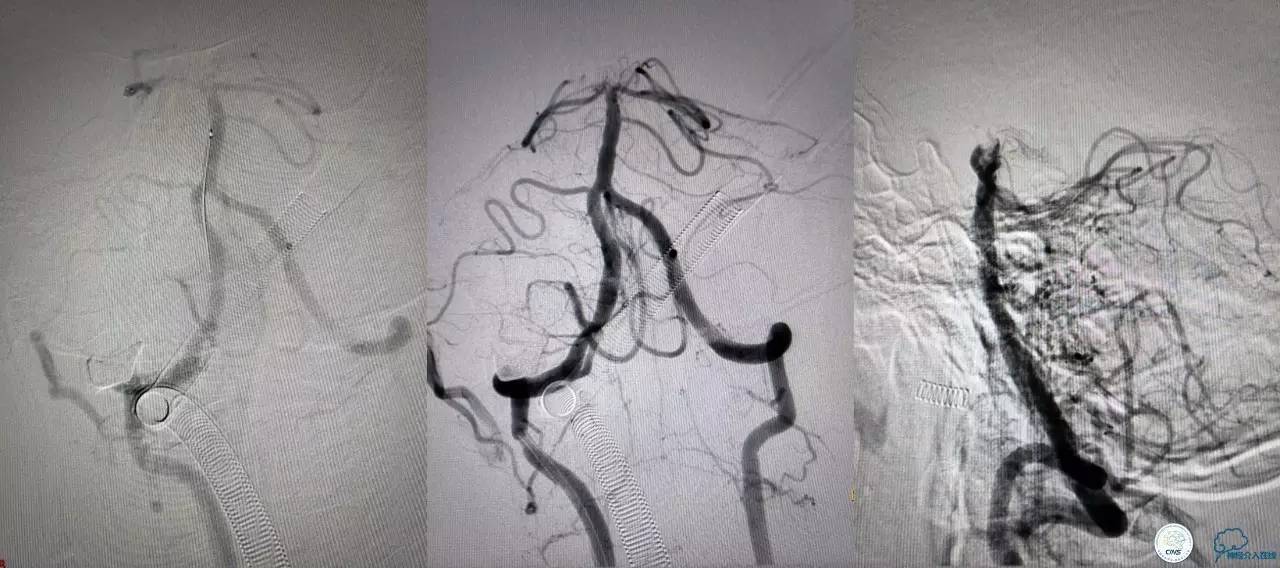

决定导管内给予替罗非班6ml,复查造影BA顶端仍闭塞,第二次取栓。

第二次取栓后可见基底动脉顶端仍有大量血栓,右侧大脑后动脉开通,但左侧大脑后未见显影且左侧小脑上动脉闭塞!

第三次取栓,支架放入左侧大脑后取栓。

第三次取栓后,左侧大脑后动脉开通,但是栓子再次栓塞右侧大脑后动脉,血栓在基地动脉顶端来回左右摆动,下一次,怎办?血栓负荷太多,可以使用solumbar技术,可以没有颅内导管,没办法,换用更大的支架6-20mm,但费用增加不少,与家属沟通后同意使用,第四次取栓:

血栓负荷还是很大,左侧大脑后再通,但右侧大脑后又闭塞,只能第五次取栓,支架放到右侧大脑后动脉更远。